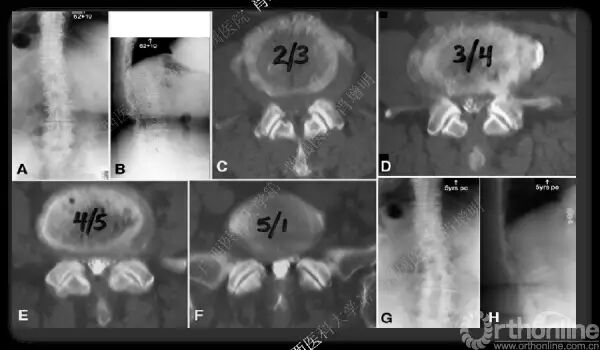

退变性脊柱侧凸是由于椎间盘退变后继发小关节退变,椎管和神经根管容积变化以及脊柱失稳,畸形等病理改变,以疼痛和神经压迫症状为主要表现的常见疾病。

退变性脊柱侧凸多发于50岁以上的中老年群体,是现代常见的老年疾病。多年来,针对该病的临床研究一直没有停步,广西医科大学第一附属医院肖增明教授细致地介绍了该病的诊疗进展。